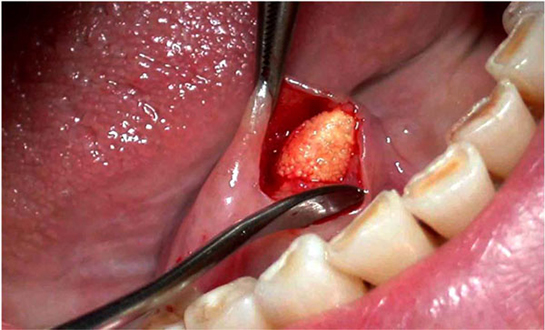

• Cerrahi müdahale: Gerekli durumlarda, tükürük bezinin drenajı veya tıkanıklığın giderilmesi için cerrahi işlem uygulanabilir.